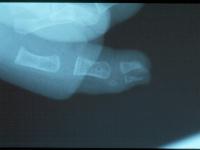

Clinical Example: Polydactyly

polydactyly